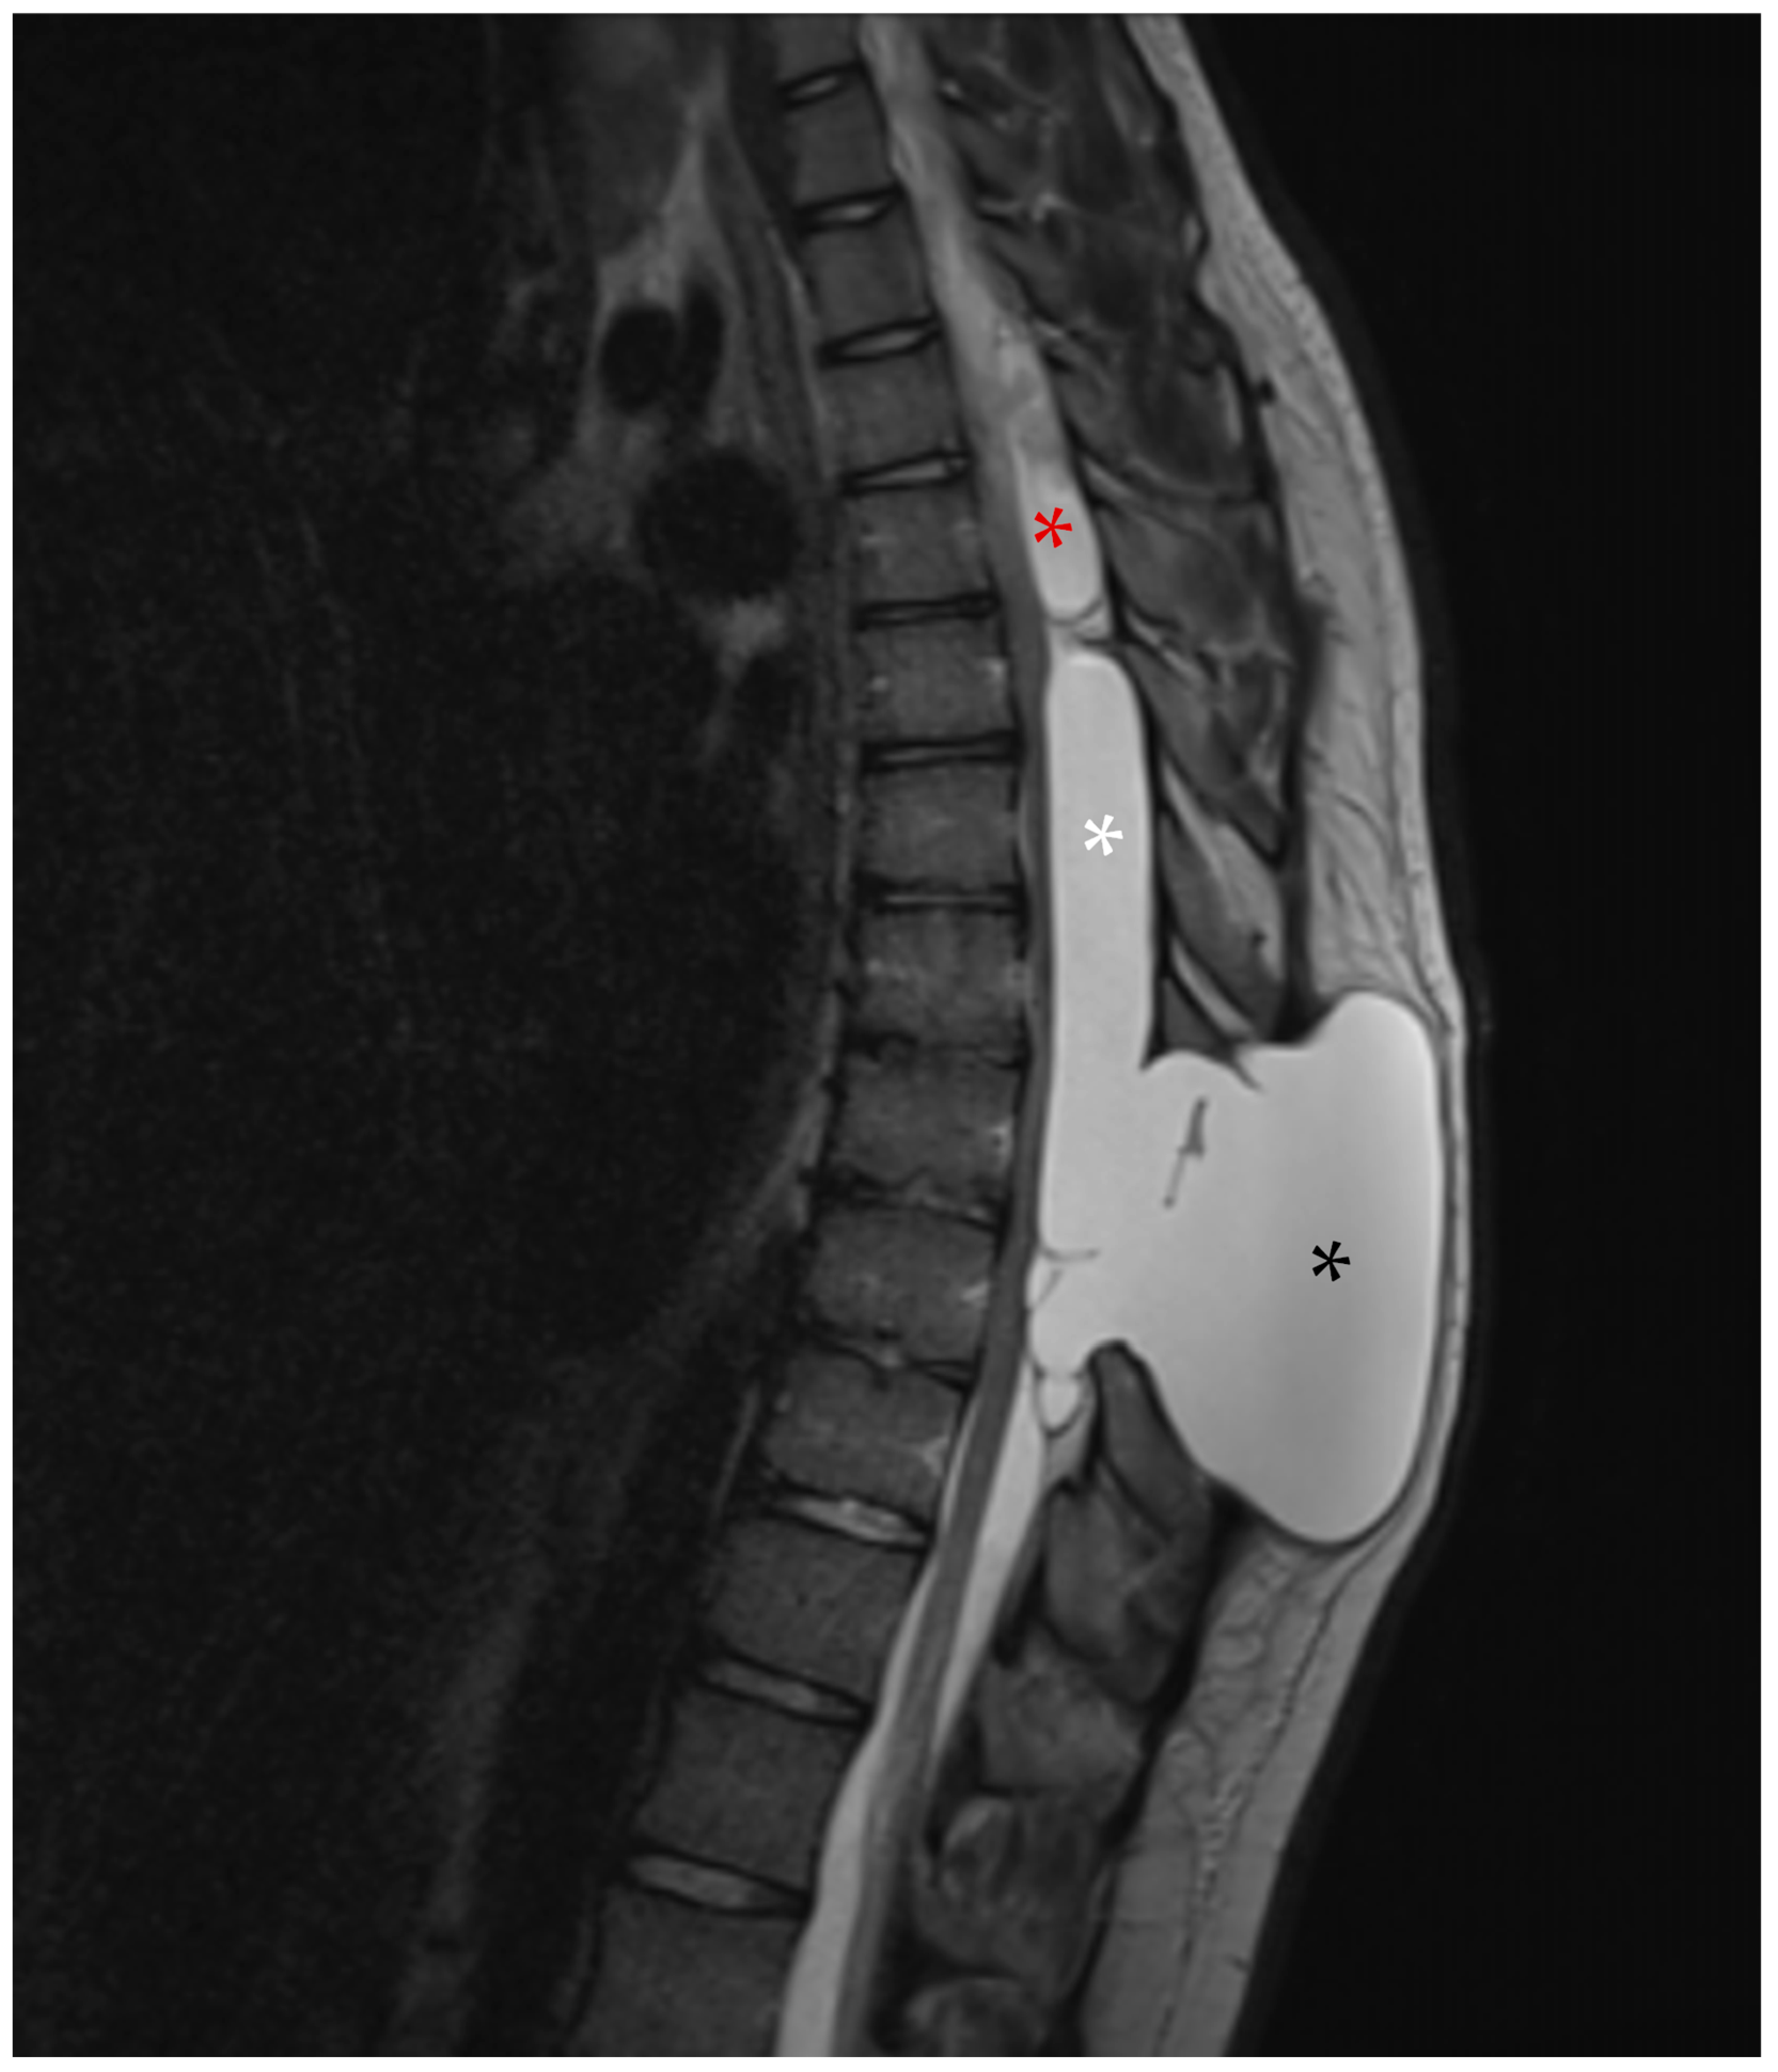

2. Case Presentation

2.1. First Admission